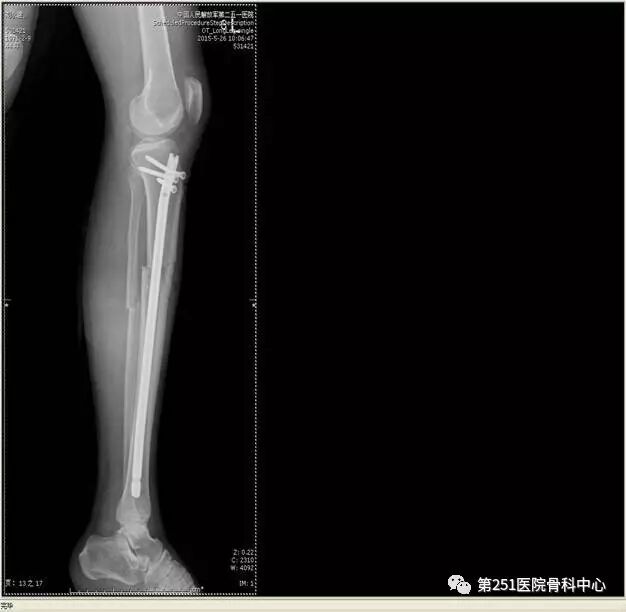

病例6:男性,39岁,车祸伤SchatzkerⅥ型胫骨平台骨折。